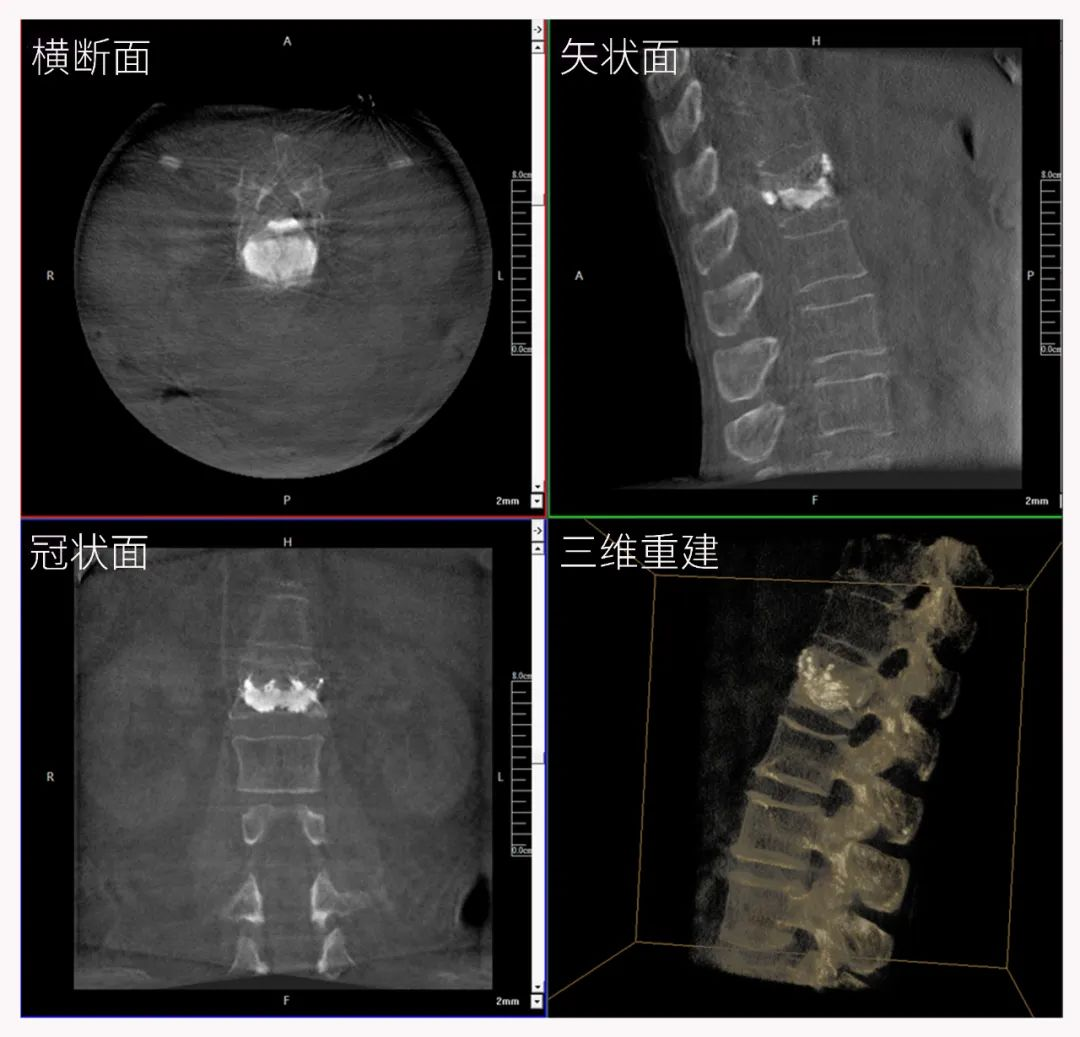

三維C形臂圖像

三維“類CT”影像

三維C形臂也被稱為“術中CT”,它具備二維C形臂的全部功能。此外,它還具備三維成像功能,三維C形臂旋轉采集多角度的二維投影數據,再通過計算機進行三維重建,能夠生成橫斷面、矢狀面、冠狀面斷層圖像以及三維立體圖像,提供更全面、更立體的解剖學信息。